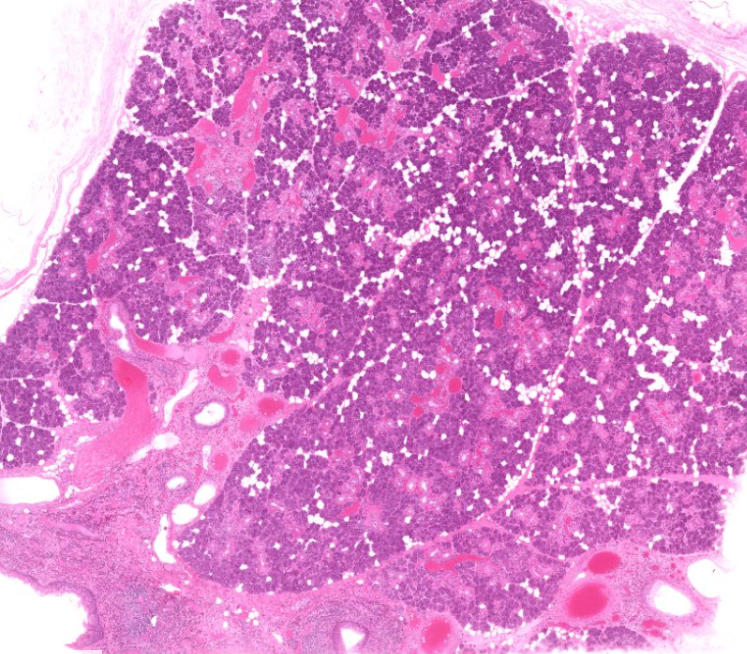

pancreas

exocrine secretes digestive enzymes

endocrine releases insulin and glucagon

lobe (red) and lobule (blue) of the pancreas

type of cell

exocrine cells of the pancreas

secrete insulin and glucagon

shaped like a slice of pie

structure

islet of Langerhans of the pancreas

endocrine cell

secrete hormones for digestion